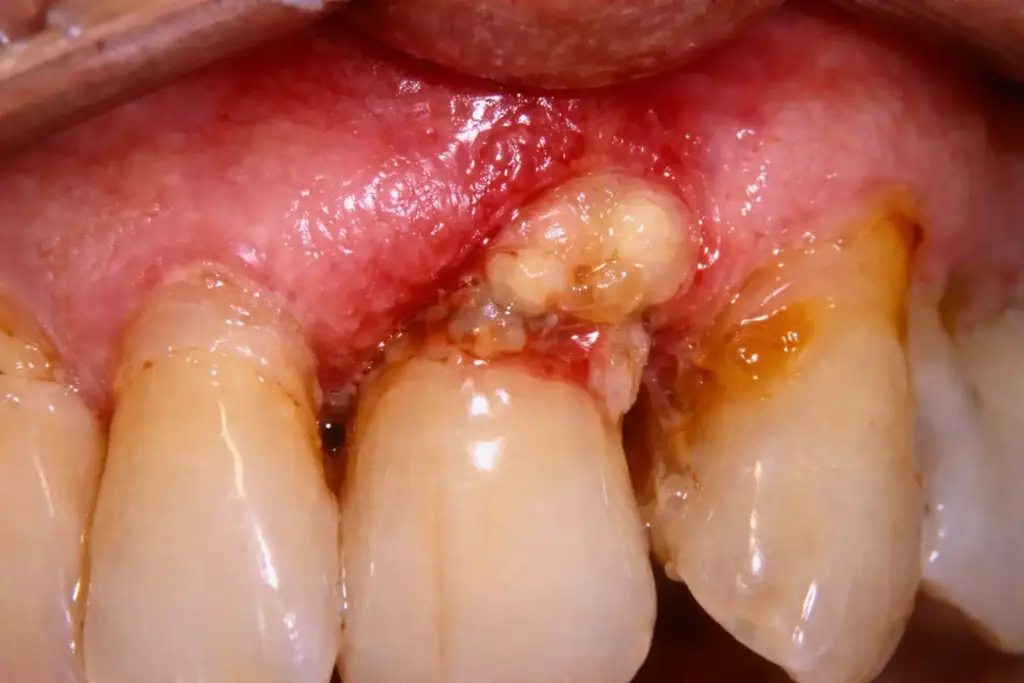

Flap surgery is a gum treatment where the gums are gently lifted to access deep infection beneath the gum line. The infected tissue, plaque, and tartar are removed, and the gums are repositioned securely to allow proper healing. This procedure helps control advanced gum disease and prevent tooth loss.

Advanced gum disease (periodontitis)

Deep gum pockets

Persistent gum infection

Bone loss around teeth